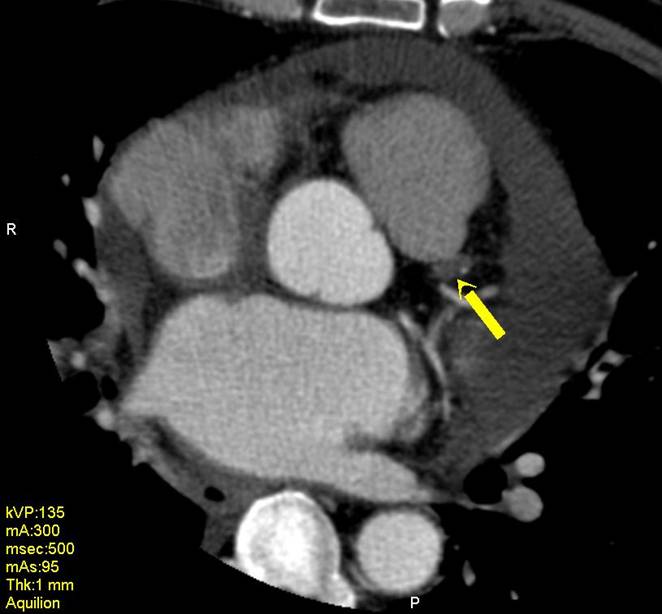

The non-invasive imaging modality of multi-detector computed tomography has dramatically evolved the last ten years and that is due to hardware and software developments. The newer generation of scanners allows increased spatial and temporal resolution that improves the clinical reliability giving further insights into the evaluation of coronary artery disease. Heart morphology imaging followed by studies of myocardial function and assessment of cardiac valves can be performed from the information derived from the data of the coronary artery examination. Also, the venous anatomy of the heart, coronary artery bypass grafts, stents, and cardiac tumors can be imaged and evaluated when necessary. For the beneficial use of this method, entrance criteria for different patient groups need to be set in order to allow improved outcome of multi-detector CT.